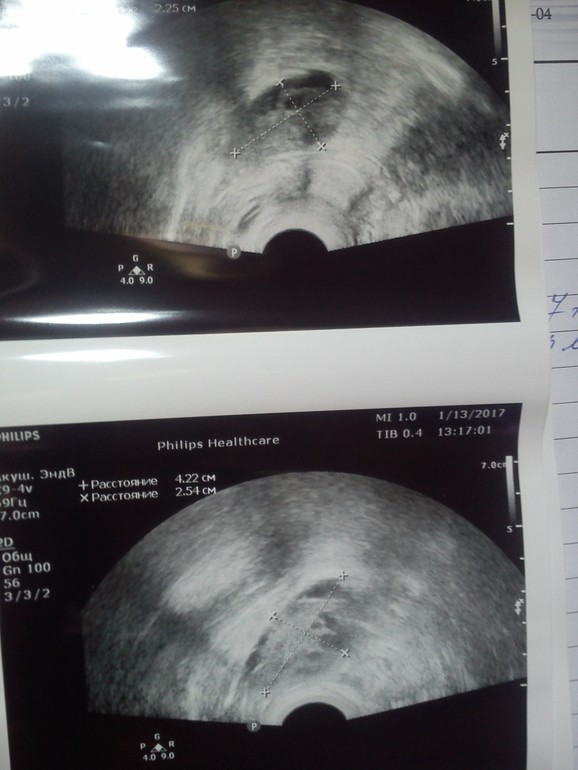

и еще вопрос: кто-то разбирается в УЗИ? фото ниже. она говорит что ДФ нет (17 ДЦ). цикл очень нерегулярный, последний был 70 дней. а сделала тест, тоже ниже, похоже что на подходе. Думаю может она спец. сказала что нет чтоб "сбить" денег? сказала что лечения нет. 14 тыс.грн. лапара....ну нет таких денег....